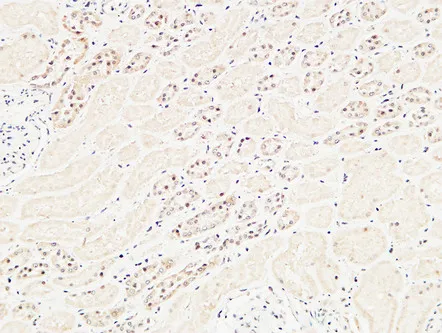

Cleaved-Caspase-9 p35 (D315) Rabbit Polyclonal Antibody

Cat: APRab08971